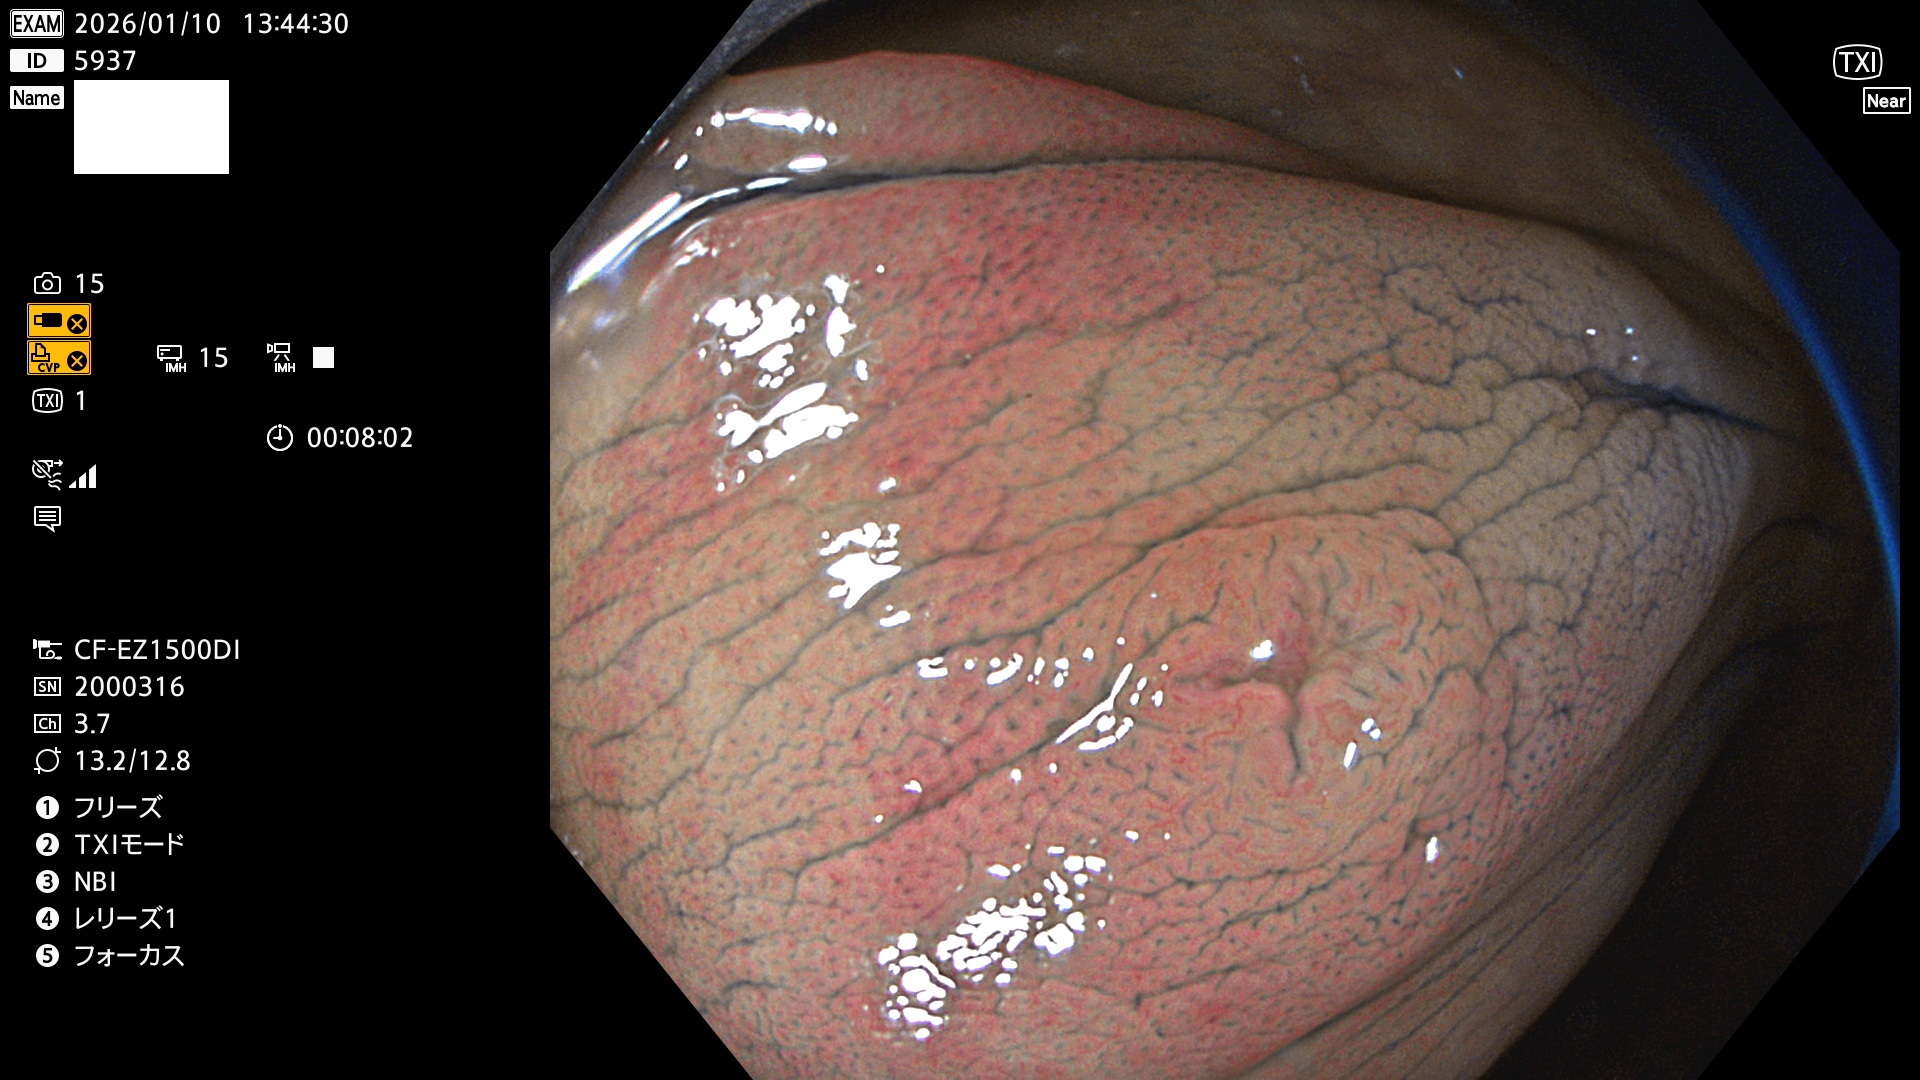

完全に平坦な物をUb、陥凹している物をUcと呼びます。Ubは認識が困難で、Ucはびらん(炎症)と紛らわしいために見落とされやすく、「内視鏡後・大腸癌」の原因になります。

専門的)Uc=De Novo癌? 内視鏡の解像度が低かった時代、このような説もありました。しかし今日の高精度内視鏡では良性の微小なUc型腺腫(APC遺伝子異常の腺腫)が日常的に見つかります。Ucこそが多段階発癌(Adenoma-Carcinoma Sequence)のMain Routeです。

毎週の検査(木・金・土・日)に発見されたUbとUc型・腺腫を、その週の日曜の夜にUPし1週間、提示します。

2026年1月8日〜1月11日の4日間(40件)6個 (Uc_ADR=6個/40人=15%)